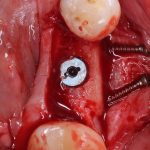

Кстати, обрати внимание на ширину альвеолярного гребня (левая картинка). Она чуть меньше 3 мм. Это объясняет, почему я засомневался в возможности установки имплантатов одновременно с остеопластикой. Понятно и без КЛКТ.

Наперво, мне нужно удалить разрушенный зуб и получить костный аутотрансплантат.

Возвращаемся к основной операционной области. Еще раз посмотрим на альвеолярный гребень, поофигеваем от его ширины и моих грандиозных планов: